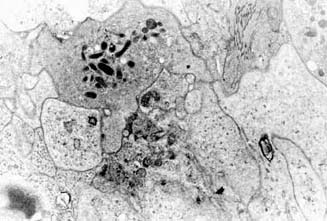

| AGREGACION PLAQUETARIA: Mosaico de plaquetas degranuladas en la pulpa esplénica roja en la primera fase de la enfermedad constituyendo un agregado plaquetario. |